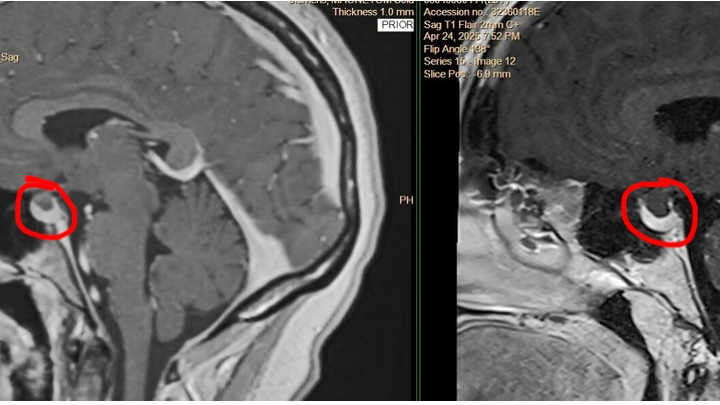

I was unexpectedly part of a mass layoff on May 19th, and shortly after, I received a life-changing diagnosis of scleroderma, a rare autoimmune condition. Now, I’m preparing to undergo brain surgery on July 17th at The James in Columbus.